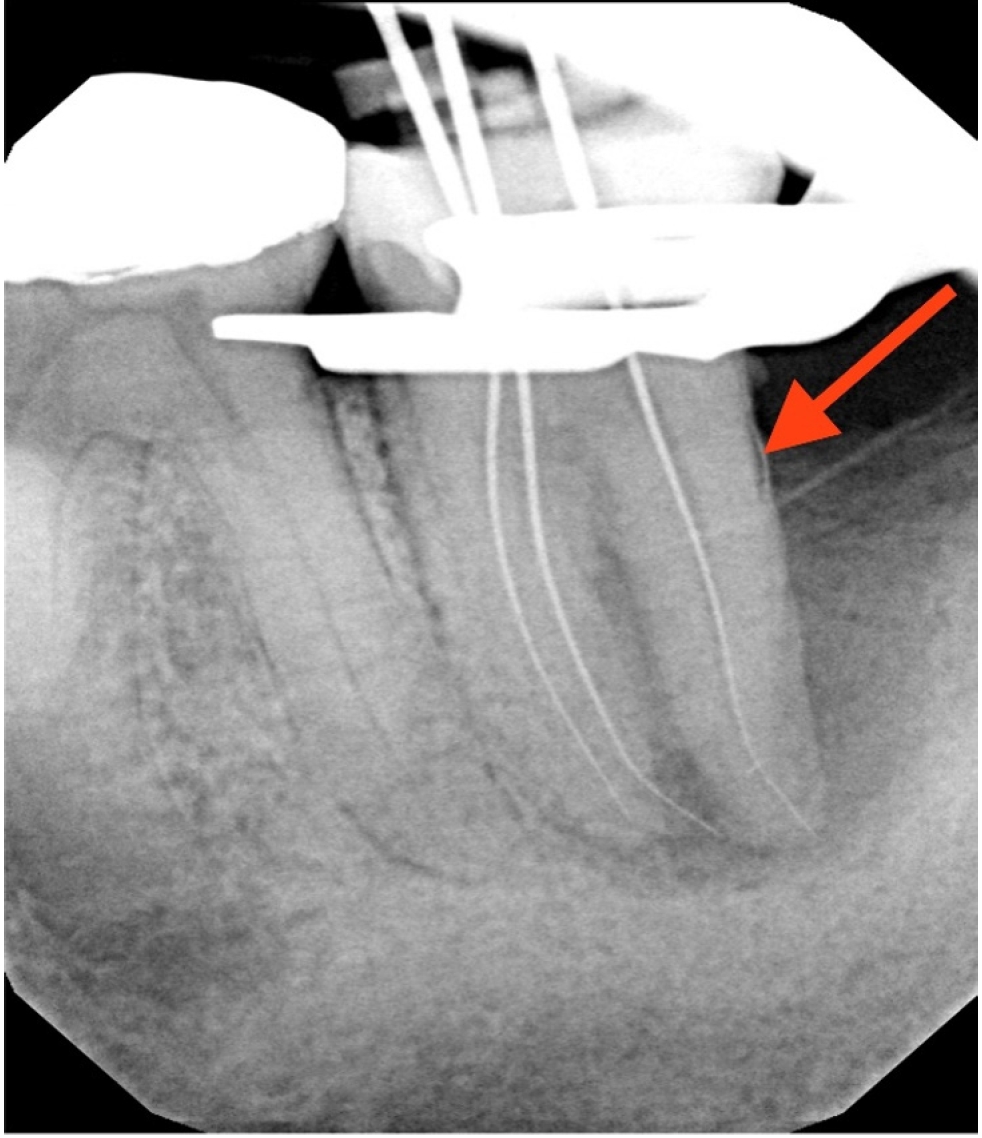

At the 2-week follow-up, the sinus tract had healed. After the same anesthesia and isolation protocol as the first visit, the tooth was accessed through the temporary restoration. Calcium hydroxide was irrigated out with 17% ethylenediaminetetraacetic acid solution, which was ultrasonically activated for 15 seconds in each canal. This was followed by 5% sodium hypochlorite irrigation, which was ultrasonically activated for 15 seconds in each canal, after which cone fit was verified clinically and confirmed with a radiograph (Figure 3). The canals were then dried with paper points, and obturation was completed using gutta-percha cones and AH Plus sealer (Dentsply DeTrey GmbH, Konstanz, Germany) with the cold lateral condensation technique. The tooth was temporized with a sterile sponge and Cavit (3M ESPE) and a postoperative radiograph was captured (Figure 4). A referral for periodontal therapy was given to the patient.

Figure 3.

Cone-fit radiograph.

Figure 3. Cone-fit radiograph.